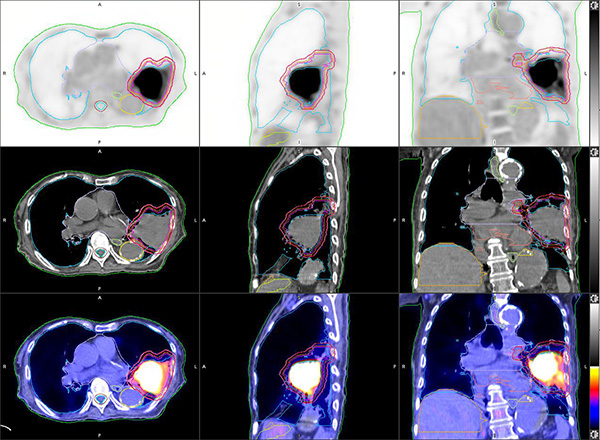

Developed in 2021 PET/CT Simulation is a one-stop imaging facility for both metabolic evaluation and CT simulation in radiotherapy treatment planning. The efficacy of radiotherapy relies on maximizing radiation dose to tumor and preserving normal tissues. With the variety of PET tracers available, PET/CT can delineate the metabolic boundary, quantify aggressiveness and characterize tissue functional status (e.g. cellular differentiation and hypoxia) of targeted tumor.

Our PET/CT scanner with SiPM technology, equipped with an external laser positioning system and a flat indexing pallet, has a precise spatial co-registration and an outstanding image quality. Image data in a single PET/CT scan can streamline the workflow and personalize treatment plan. Biological tumor contours and functional data on PET images can be transferred directly to CT images for dosimetric calculation and dose boosting. It can it be used at pre-treatment stage and within treatment course for interim assessment and adaptive planning.